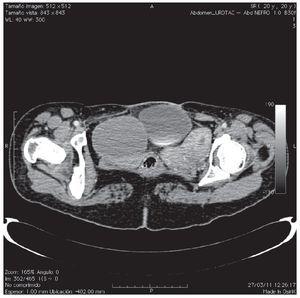

Paciente femenino de 20 años de edad, antecedente de extrofia vesical con cierre espontáneo. A la exploración física, se encuentra la presencia de duplicación de genitales internos y externos (clítoris, vaginas, útero), así como falta de fusión de la pelvis ósea (Figura 1). Paciente acudió al servicio de urología, por la presencia de dolor en el flanco derecho y una masa palpable. Se le realizó tomografía, donde se evidenció una bolsa hidronefrótica derecha y la presencia de dos vejigas con uretras independientes y un útero doble (Figuras 2 y 3). En la resonancia magnética, se pudieron identificar dos vejigas no comunicantes con interface entre las dos (Figuras 4 y 5). Se envió a genética reportándose cariotipo de 46XX. Se realizó cistografía, donde se evidenció la presencia de duplicación vesical completa y presencia de reflujo vesicoureteral derecho grado IV. Se realizó cistoscopia con lente pediátrico de 30 grados, observando en la uretra derecha hemivejiga con meato ureteral ortotópico dilatado, sin visualizarse el izquierdo, ni conexión a hemivejiga izquierda. Se realizó el mismo procedimiento en la uretra izquierda, visualizando uréter ortotópico y eyaculante. Se diagnosticó doble sistema genitourinario completo, con reflujo vesicoureteral grado IV y exclusión renal derecha. Se programó para nefroureterocistectomía derecha.

Figura 3. El corte tomográfico de abdomen inferior, muestra dos vejigas.